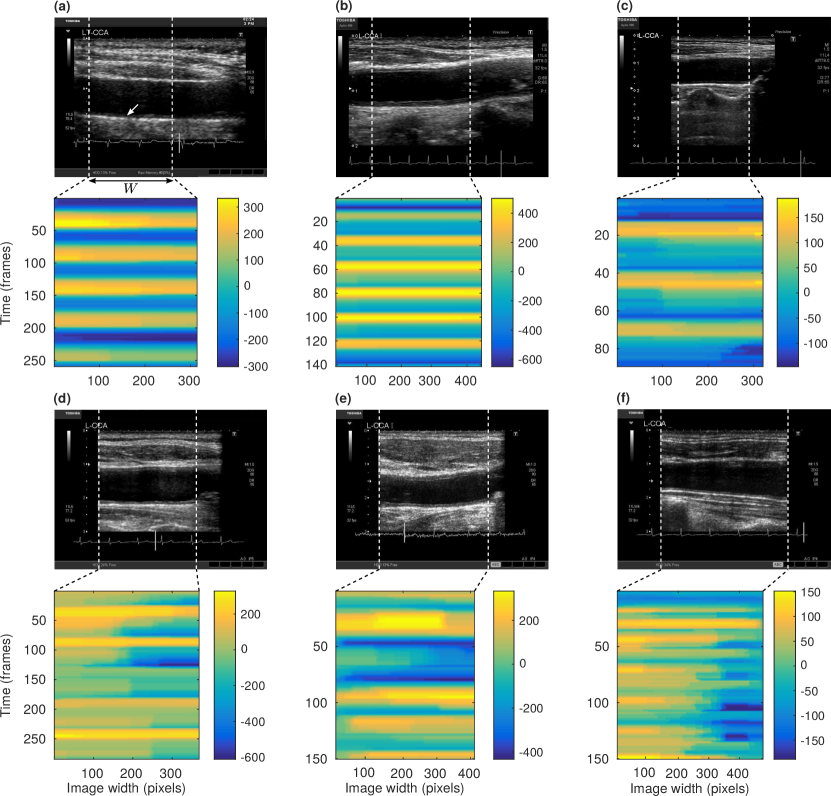

The very nature of the DBM framework enabled for the extraction of a dense motion field . Several dynamic patterns, corresponding to different participants, are displayed in Figure 7. Although a quantitative analysis of the tracking accuracy was only performed in three local points per cine-loop, as described above, a qualitative assessment of the motion homogeneity can be obtained from these 2D fields.

The association between either the motion inhomogeneity index or the peak-to-peak amplitude and participants characteristics is provided in Table 4. The strongest correlates to were coronary artery disease (, , Figure 8) and systolic blood pressure (, ). Interestingly, the association with coronary artery disease remained nearly-significant (, ) in a multivariable model after adjusting for systolic blood pressure and peak systolic value, the second and third strongest independent correlates. The peak-to-peak amplitude was strongly correlated with peripheral artery disease (, ) and hypertension (, ). These results are in accordance with previous findings showing that is associated with cardiovascular risk factors zahnd2012longitudinal . A significant association was also observed between and (, ). A qualitative analysis of the motion field in all participants did not reveal an association between motion homogeneity and putative local tissue stiffness (e.g. healthy sections or atherosclerotic plaques, Figure 7).